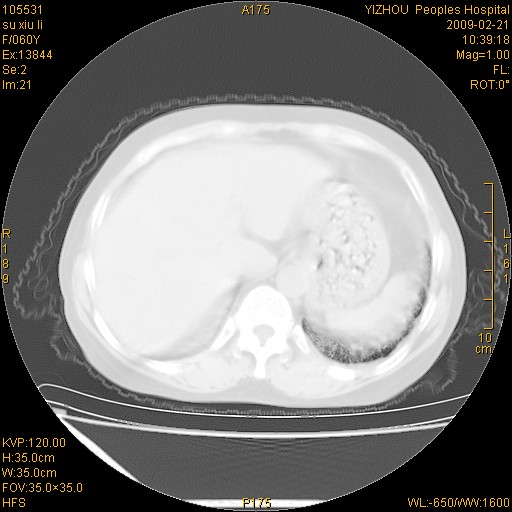

标题: CT18259:两肺间质纤维化? [打印本页]

标题: CT18259:两肺间质纤维化?

女,60岁,反复咳嗽1月。

两肺支扩,以肺为著合并双肺较广范纤维化病变。建议除外结核等病变。

间质性肺炎

符合间质感染,部分纤维化表现

特发性间质纤维化

特发性间质纤维化伴支扩!

间质性肺炎或特发性间质性肺炎